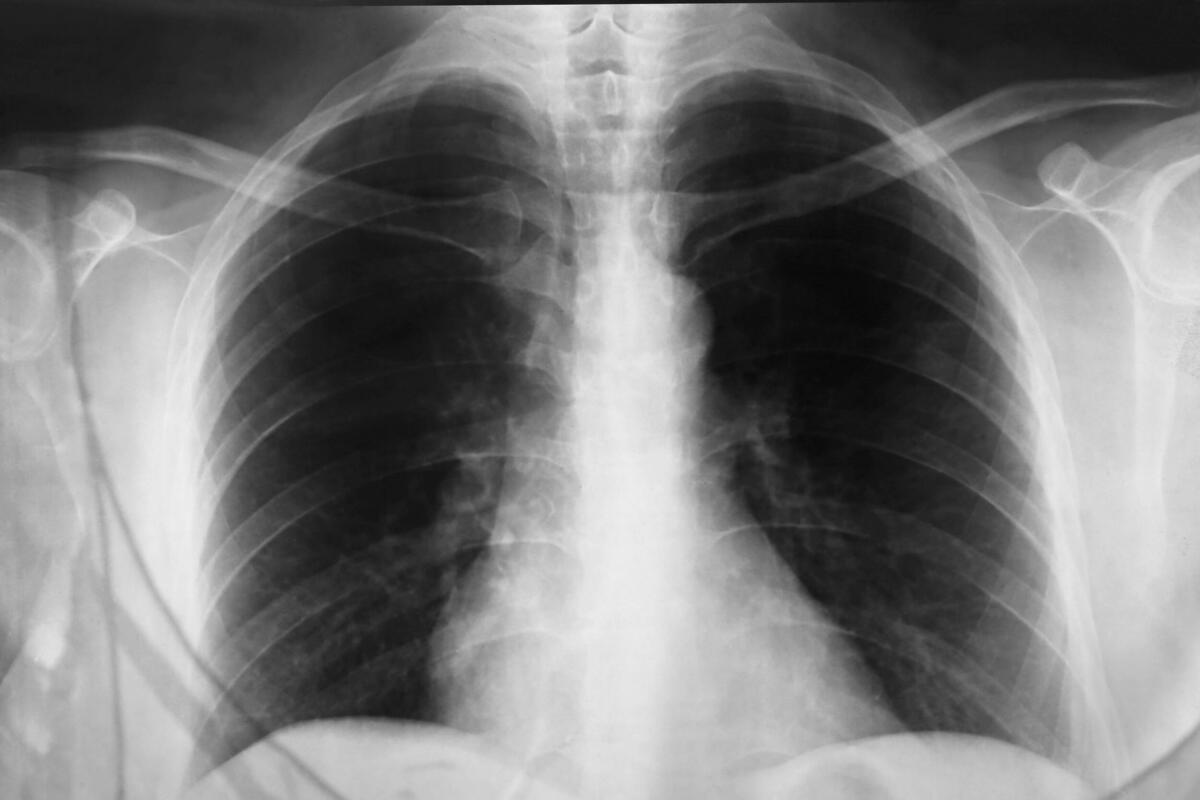

Upala pluća, poznata i kao pneumonija, jedna je od najpasnijih respiratornih infekcija jer može zahvatiti ljude svih uzrasta i razviti se iz obične prehlade ili gripa.

Upala pluća najčešće počinje kao infekcija koja polako zahvata disajne puteve, a zatim prelazi na plućno tkivo. U početku simptomi mogu biti blagi i lako se zamijeniti običnom prehladom, zbog čega mnogi ne traže ljekarsku pomoć na vrijeme.

Jedan od najprepoznatljivijih simptoma je kašalj, koji može biti suh na početku, a zatim postaje uporan i bolan. Što je infekcija jača, disanje postaje otežano i plitko. Osoba može osjetiti pritisak ili bol u grudima, naročito pri kašlju ili dubokom udahu. Još jedan čest znak je ubrzano disanje, jer pluća više ne mogu normalno obavljati svoj posao. Kako se upala širi, tijelo pokušava nadoknaditi manjak kisika, što dodatno iscrpljuje organizam.

Ako se pneumonija u vrijeme ne prepozna i može dovesti do teških neliječih komplikacija. Upala može zahvatiti više dijelova pluća, što otežava dotok kisika u krv. U najtežim slučajevima može doći do otkazivanja vitalnih organa jer tijelo više ne može dobiti dovoljno kisika za normalno funkcionisanje. Tada dolazi do naglog pogoršanja stanja, pacijent može u vrlo kratkom roku postati životno ugrožen. Upravo je takav scenario bio fatalan i za slavnu glumicu koja je izgubila bitku s ovom bolešću, podsjećajući svijet da ni slava ni bogatstvo ne mogu zaštititi od komplikacija neprepoznate infekcije.

Upala pluća može biti bakterijska, virusna ili gljivična, a svaka vrsta zahtijeva drugačiji pristup liječenju. Zbog toga je ključno da se ne uzimaju lijekovi na svoju ruku, jer pogrešan tretman može samo pogoršati stanje. Nerijetko ljudi pokušavaju da ublaže simptome kućnim metodama, vjerujući da se radi o običnoj gripi, i tako izgube dragocjeno vrijeme. Ljekari naglašavaju da se svaki kašalj koji traje duže od nekoliko dana, praćen visokom temperaturom, bolovima u grudima i otežanim disanjem, mora shvatiti ozbiljno.